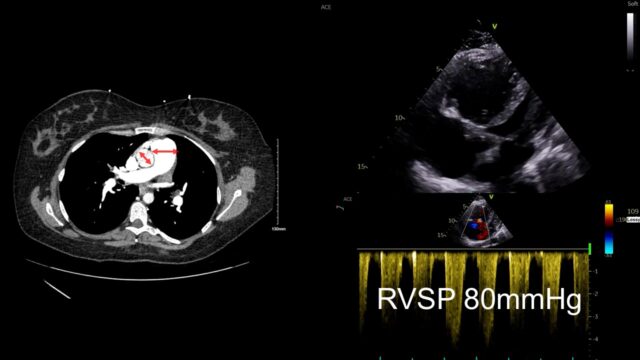

Look further and you can see the main PA is much bigger than the aorta, that takes time to develop. When you look with echo you can see a massive RV but it’s big and chunky and looks like its been lifting kettle bells for years. The bottom is a little doppler way of measuring right sided heart pressures and it suggested that the right heart pressures were far too high for this to be an acute event. This case is actually someone with primary pulmonary hypertension that just happened to have a PE.

I have dedicated more of my career than I would like to admit to echocardiography so it’s hardly surprising that i think you should reach for an echo in PE. My impression from both EM and critical care perspective is that our trainees are now coming out of training with a reliable set of skills to do this. The echo will answer your question – is this hypotensive patient with a PE on CT scan actually dying from PE or is it from something else. I think it’s probably better than CT at teasing out how bad the heart is. It also allows you to assess your therapies to assess if they’re getting better or not.

These images are all from a young female with high risk PE with pre and post lysis images. In a revolution of AI assited imaging they now come with added labels…

This is PSSAX view. In a life threatening PE the RV enlarges, the right sided pressures rise and the interventricular septum loses its roundness and becomes flat. This is the D sign you might here of. Like a capital D tilted over slightly.